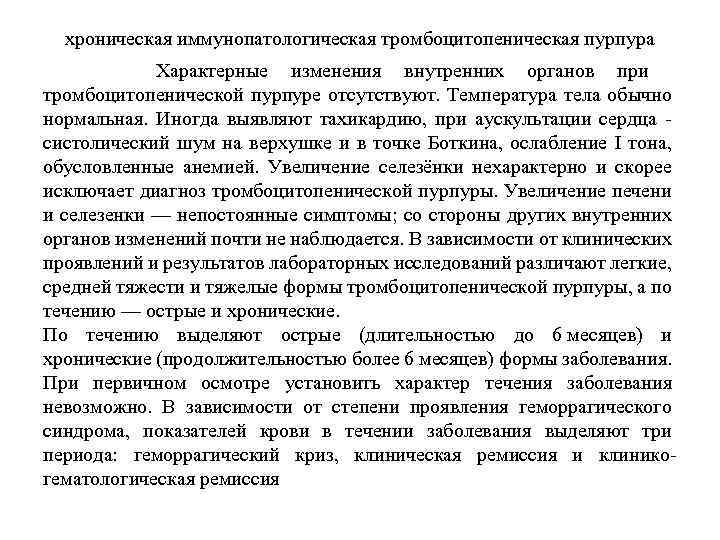

хроническая иммунопатологическая тромбоцитопеническая пурпура Характерные изменения внутренних органов при тромбоцитопенической пурпуре отсутствуют. Температура тела обычно нормальная. Иногда выявляют тахикардию, при аускультации сердца - систолический шум на верхушке и в точке Боткина, ослабление I тона, обусловленные анемией. Увеличение селезёнки нехарактерно и скорее исключает диагноз тромбоцитопенической пурпуры. Увеличение печени и селезенки — непостоянные симптомы; со стороны других внутренних органов изменений почти не наблюдается. В зависимости от клинических проявлений и результатов лабораторных исследований различают легкие, средней тяжести и тяжелые формы тромбоцитопенической пурпуры, а по течению — острые и хронические. По течению выделяют острые (длительностью до 6 месяцев) и хронические (продолжительностью более 6 месяцев) формы заболевания. При первичном осмотре установить характер течения заболевания невозможно. В зависимости от степени проявления геморрагического синдрома, показателей крови в течении заболевания выделяют три периода: геморрагический криз, клиническая ремиссия и клиникогематологическая ремиссия